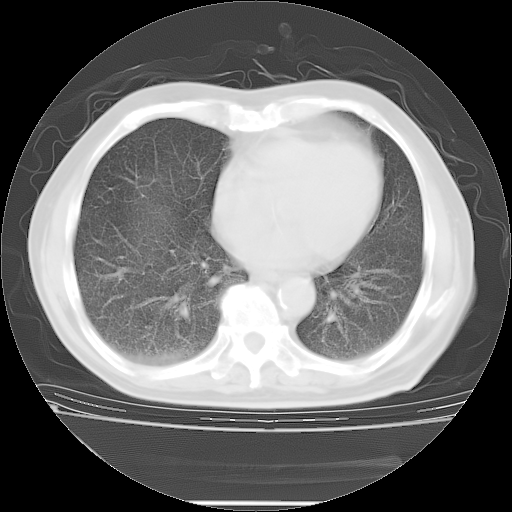

今天复查肺部CT,发现双肺广泛磨玻璃样改变。所以我把3月19日和5月9日相隔50天的肺部CT上传。请大家会诊。

5月9日肺部CT(在4月27日齐鲁医院肺部CT描述部分肺组织磨玻璃样改变,12天后肺组织广泛磨玻璃样改变)

大致读了系列胸部CT:纵隔窗无明显异常,肺窗:从4、27至今:主要是双肺中下野外带可见毛玻璃样改变,目前处于急性肺泡炎阶段,至于原因考虑1、结替组织或胶原血管性疾病所致?2、恶性疾病如恶组在肺部所致的表现或细支气管肺泡癌?3、药物或其它原因如肺蛋白沉着症所致肺泡炎目前不太可能?总之,明天就去请我院的呼吸科、感染科、血液科和临免专家会诊哈。